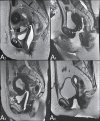

Magnetic resonance imaging is a method with high contrast resolution widely used in the assessment of pelvic gynecological diseases. However, the potential of such method to diagnose vaginal lesions is still underestimated, probably due to the scarce literature approaching the theme, the poor familiarity of radiologists with vaginal diseases, some of them relatively rare, and to the many peculiarities involved in the assessment of the vagina. Thus, the authors illustrate the role of magnetic resonance imaging in the evaluation of vaginal diseases and the main relevant findings to be considered in the clinical decision making process.